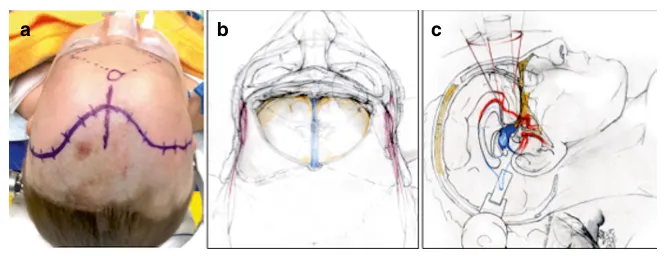

图:额底中线开颅联合纵裂入路示意图,显示患者体位、皮肤切口、开颅范围及经纵裂抵达视交叉-下丘脑区域的路径。

额底中线开颅联合纵裂入路技术解析

患者取仰卧位,抬高下肢及上半身,头部略向后伸展。皮肤切口标记在发际线后方,除既往手术遗留局部瘢痕者外,通常为双侧对称切口。儿童与青少年或成人患者的区别在于年幼儿童无额窦,这简化了额底中线开颅。

青少年及成人通常有大小不一的额窦,必须在开颅和手术结束关颅时予以考虑。术前CT扫描可清晰显示额窦的大小、形状和范围;术中,在神经导航辅助下确定其上界和外侧界。切开皮肤后,将额部皮瓣翻向下至眶缘。在高位额部区域及沿双侧颞上线切开骨膜,并同样向下翻至眶缘水平。由此获得一个带血管蒂的骨膜瓣,在手术结束时硬脑膜水密缝合后,可用其立即覆盖额窦(额窦颅腔化)。

需注意清除骨瓣上所有残留的额窦黏膜,以防术后形成黏液囊肿。开颅并悬吊硬脑膜后,从外侧向内侧切开硬脑膜,结扎上矢状窦,并切断大脑镰在鸡冠的附着点。仔细离断双侧嗅神经周围的蛛网膜,使其与额叶分离。在逐步分离纵裂内蛛网膜后,即可在不牵动嗅神经的情况下向侧方牵开额叶,从而在整个硬膜内手术过程中保留嗅神经。

如此,获得了对视神经、视交叉及Willis环前部的宽敞暴露,肿瘤前部亦可直接抵达。为暴露第三脑室内肿瘤,从下方的视交叉向上至前连合打开终板。对于有明显侧方延伸的病变,曾离断前交通动脉。此操作允许额外的侧方牵拉和安全的肿瘤切除。

此颅底入路的优势在于可获得下丘脑区域的全景视野,不仅能直线、对称地深入第三脑室,还能抵达脚间池和鞍区。与眶颧技术类似,额底纵裂入路更为费力耗时;尽管如此,其同样能提供良好的美观效果。